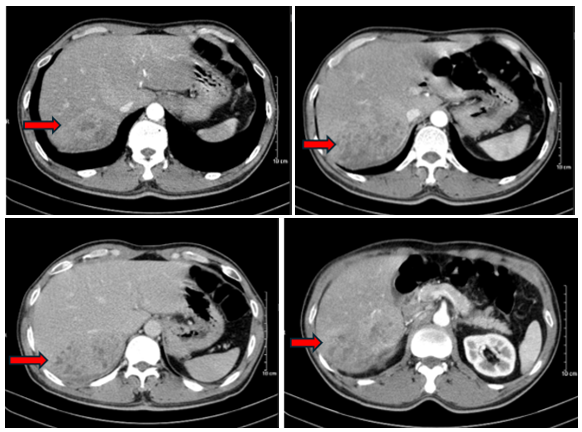

- Cắt lớp vi tính ổ bụng:

Hình 1: U gan phân thùy sau thể thâm nhiễm kích thước 58x80x77 mm tính chất ngấm thuốc dạng HCC (ung thư biểu mô tế bào gan) (mũi tên đỏ), khối xâm lấn gây huyết khối tĩnh mạch cửa nhánh phân thùy sau.

Nhận xét: Đây là một trường hợp bệnh nhân vào viện vì đau hạ sườn phải đi khám phát hiện u gan, trên hình ảnh Cắt lớp vi tính ổ bụng, u gan có tính chất điển hình của UTBMTBG + AFP tăng cao hơn mức bình thường (nhưng < 400 ng/ml) + có nhiễm viêm gan B. Theo hướng dẫn chẩn đoán và điều trị ung thư biểu mô tế bào gan của Bộ Y tế năm 2020, trường hợp này đáp ứng một trong ba tiêu chuẩn chẩn đoán xác định.